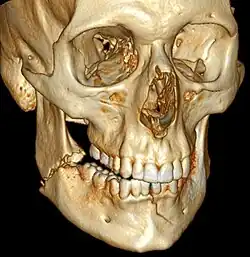

![]() | |

| 3D computed tomographic image of a mandible fracture in two places. One is a displaced right angle fracture and the other is a left parasymphyseal fracture. | |

Computed tomography

Computed tomography is the most sensitive and specific of the imaging techniques. The facial bones can be visualized as slices through the skeletal in either the axial, coronal or sagittal planes. Images can be reconstructed into a 3-dimensional view, to give a better sense of the displacement of various fragments. 3D reconstruction, however, can mask smaller fractures owing to volume averaging, scatter artifact and surrounding structures simply blocking the view of underlying areas.